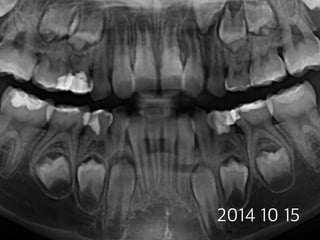

#54,#74,#84 pulpotomy

(8 female)

2012 03 27

2014 10 15

#74 2012 12 21

#84 2013 05 28

2014 07 17

#54

#74

#84

22m later

16m later

3m later